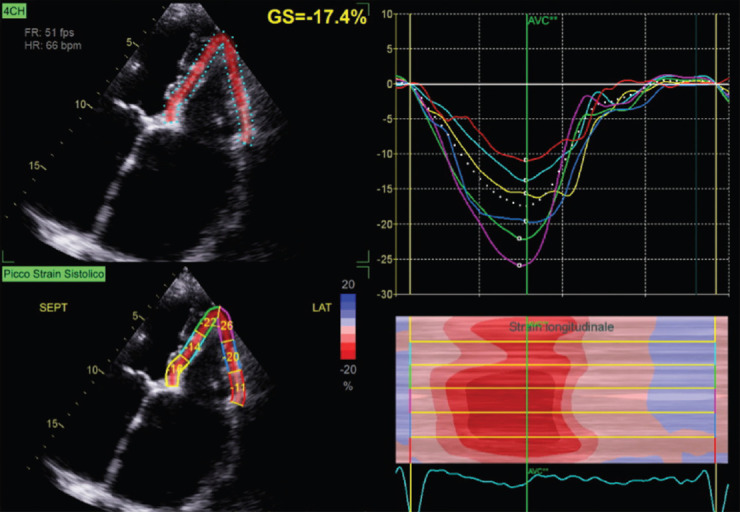

Abstract Image